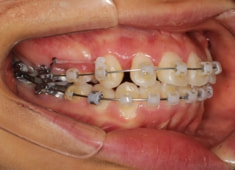

治療開始時